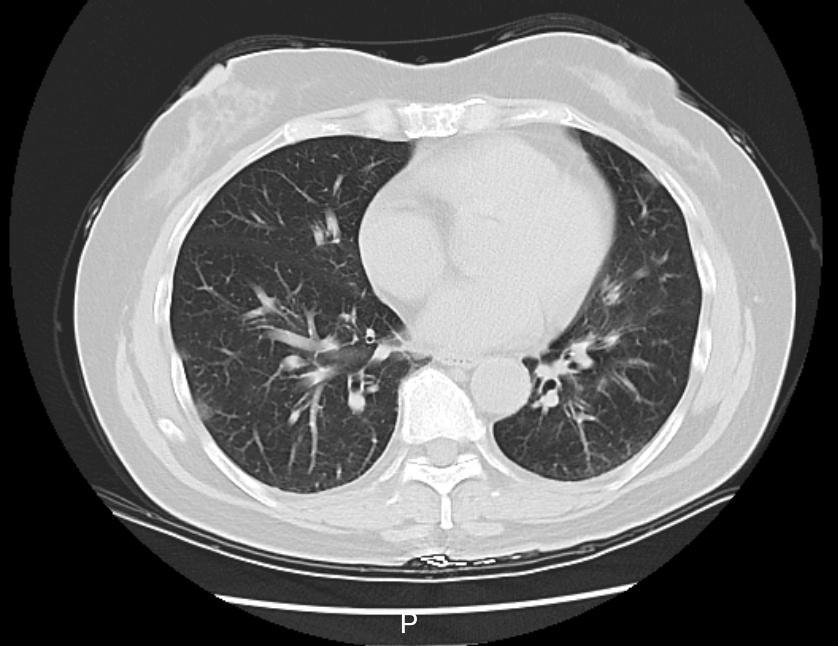

接诊的庞医生了解到,李阿姨在当地接受了一些治疗,但体温仍居高不下。家中同行的6个人,有5个人都先后发烧了。庞医生判断,李阿姨大概率是得了传染性较强的呼吸道疾病,立即给她安排了血常规、相关病毒抗原检测,以及更清晰的肺部CT检查,以便进一步了解病情。

检测结果显示,李阿姨已经得了病毒性肺炎,甲型流感病毒核酸呈阳性。这一下,罪魁祸首找到了,是甲流搞砸了这一家人一次本该圆满的旅行。

图片图|李阿姨肺部CT影像